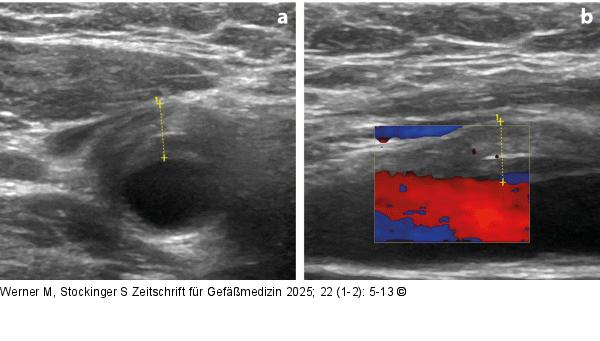

Abbildung 2a-b: Sonographie bei TIPIC-Syndrom Typisches sonographisches Bild bei TIPIC-Syndrom. (a): Querschnitt im B-Modus; (b): Längsschnitt im Color-Duplex. |

Typisches sonographisches Bild bei TIPIC-Syndrom. (a): Querschnitt im B-Modus; (b): Längsschnitt im Color-Duplex. |